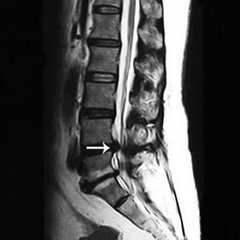

椎管狭窄引起的马尾神经压迫。很多中老年人会患有腰椎管狭窄症,腰椎管狭窄会压迫神经,导致一系列症状。腰椎管狭窄症多见于中老年人,是腰腿疼和下肢行走无力的常见原因。腰椎管狭窄患者行走过程中,会出现腰腿疼痛和下肢酸困、麻木、无力、跛行,下面为您具体分析腰椎管狭窄压迫神经有什么症状表现。》》》百看不如一问,云骨专家在线免费为你解答疑惑

3、马尾神经压迫症:腰椎管狭窄症可导致马尾神经受压迫,出现马鞍区的症状与体征以及括约肌的症状,严重时可出现大小便及性生活障碍症状。》》》百看不如一问,咨询专家如何对症治疗